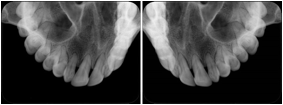

Intra-oral radiography typically involves acquisition of multiple images of various parts of the dentition. Many digital radiographic systems offer customized templates that are used for displaying the images in a study on the screen. These templates may also be referred to as mounts or view sets. The Structured Display Object represents a standard method of encoding and exchanging the layout and intended display of Structured Displays. A structured display object created in this manner could be stored with a study and exchanged with images to allow for complete reproduction of the original exam.

3. A dental provider wishes to capture a series of DICOM IO images for the patient’s dentition. The tooth morphology, teeth are divided into molars, premolars, canines and incisors, and a number of images for each jaw. The anatomic information was captured utilizing the triplet of schema. This standard code sequence is based on ISO 3950-2010, Dentistry - Designation system for teeth and areas of the oral cavity.

Every IO image should have anatomic information either through the primary or modifier sequence.

In most standard cases, images are oriented in structured layouts. These structured displays are useful to be shared between providers for reference purposes.

Table OO.1.1-1 shows structured display standard templates, where Viewset ID is based on the Japanese Society for Oral and Maxillofacial Radiology (JSOMR) classification provided by JIRA (Japan Medical Imaging and Radiological Systems Industries Association, www.jira-net.or.jp). Expected or typical teeth to be imaged location, region and designation codes are based on ISO 3950-2010, Dentistry - Designation system for teeth and areas of the oral cavity. For all the hanging protocols listed in OO.1.1-1, the value to use for Hanging Protocol Creator (0072,0008) is "JSOMR" and the value to use for Hanging Protocol Name (0072,0002) does not include "JSOMR" (e.g., "DL-S001A", not "JSOMR DL-S001A").